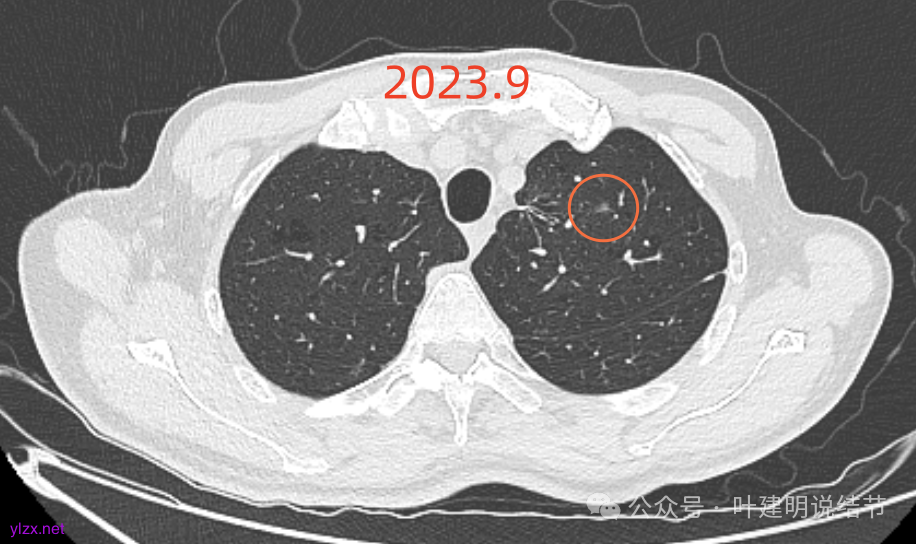

再看2024年9月的:

右上的较前略增大,且有空泡征较豙明显些,肿瘤的成分仍是纯磨密度。

左上病灶也是较为纯的,边缘不光滑,大小似乎略大一点点,不太显著。